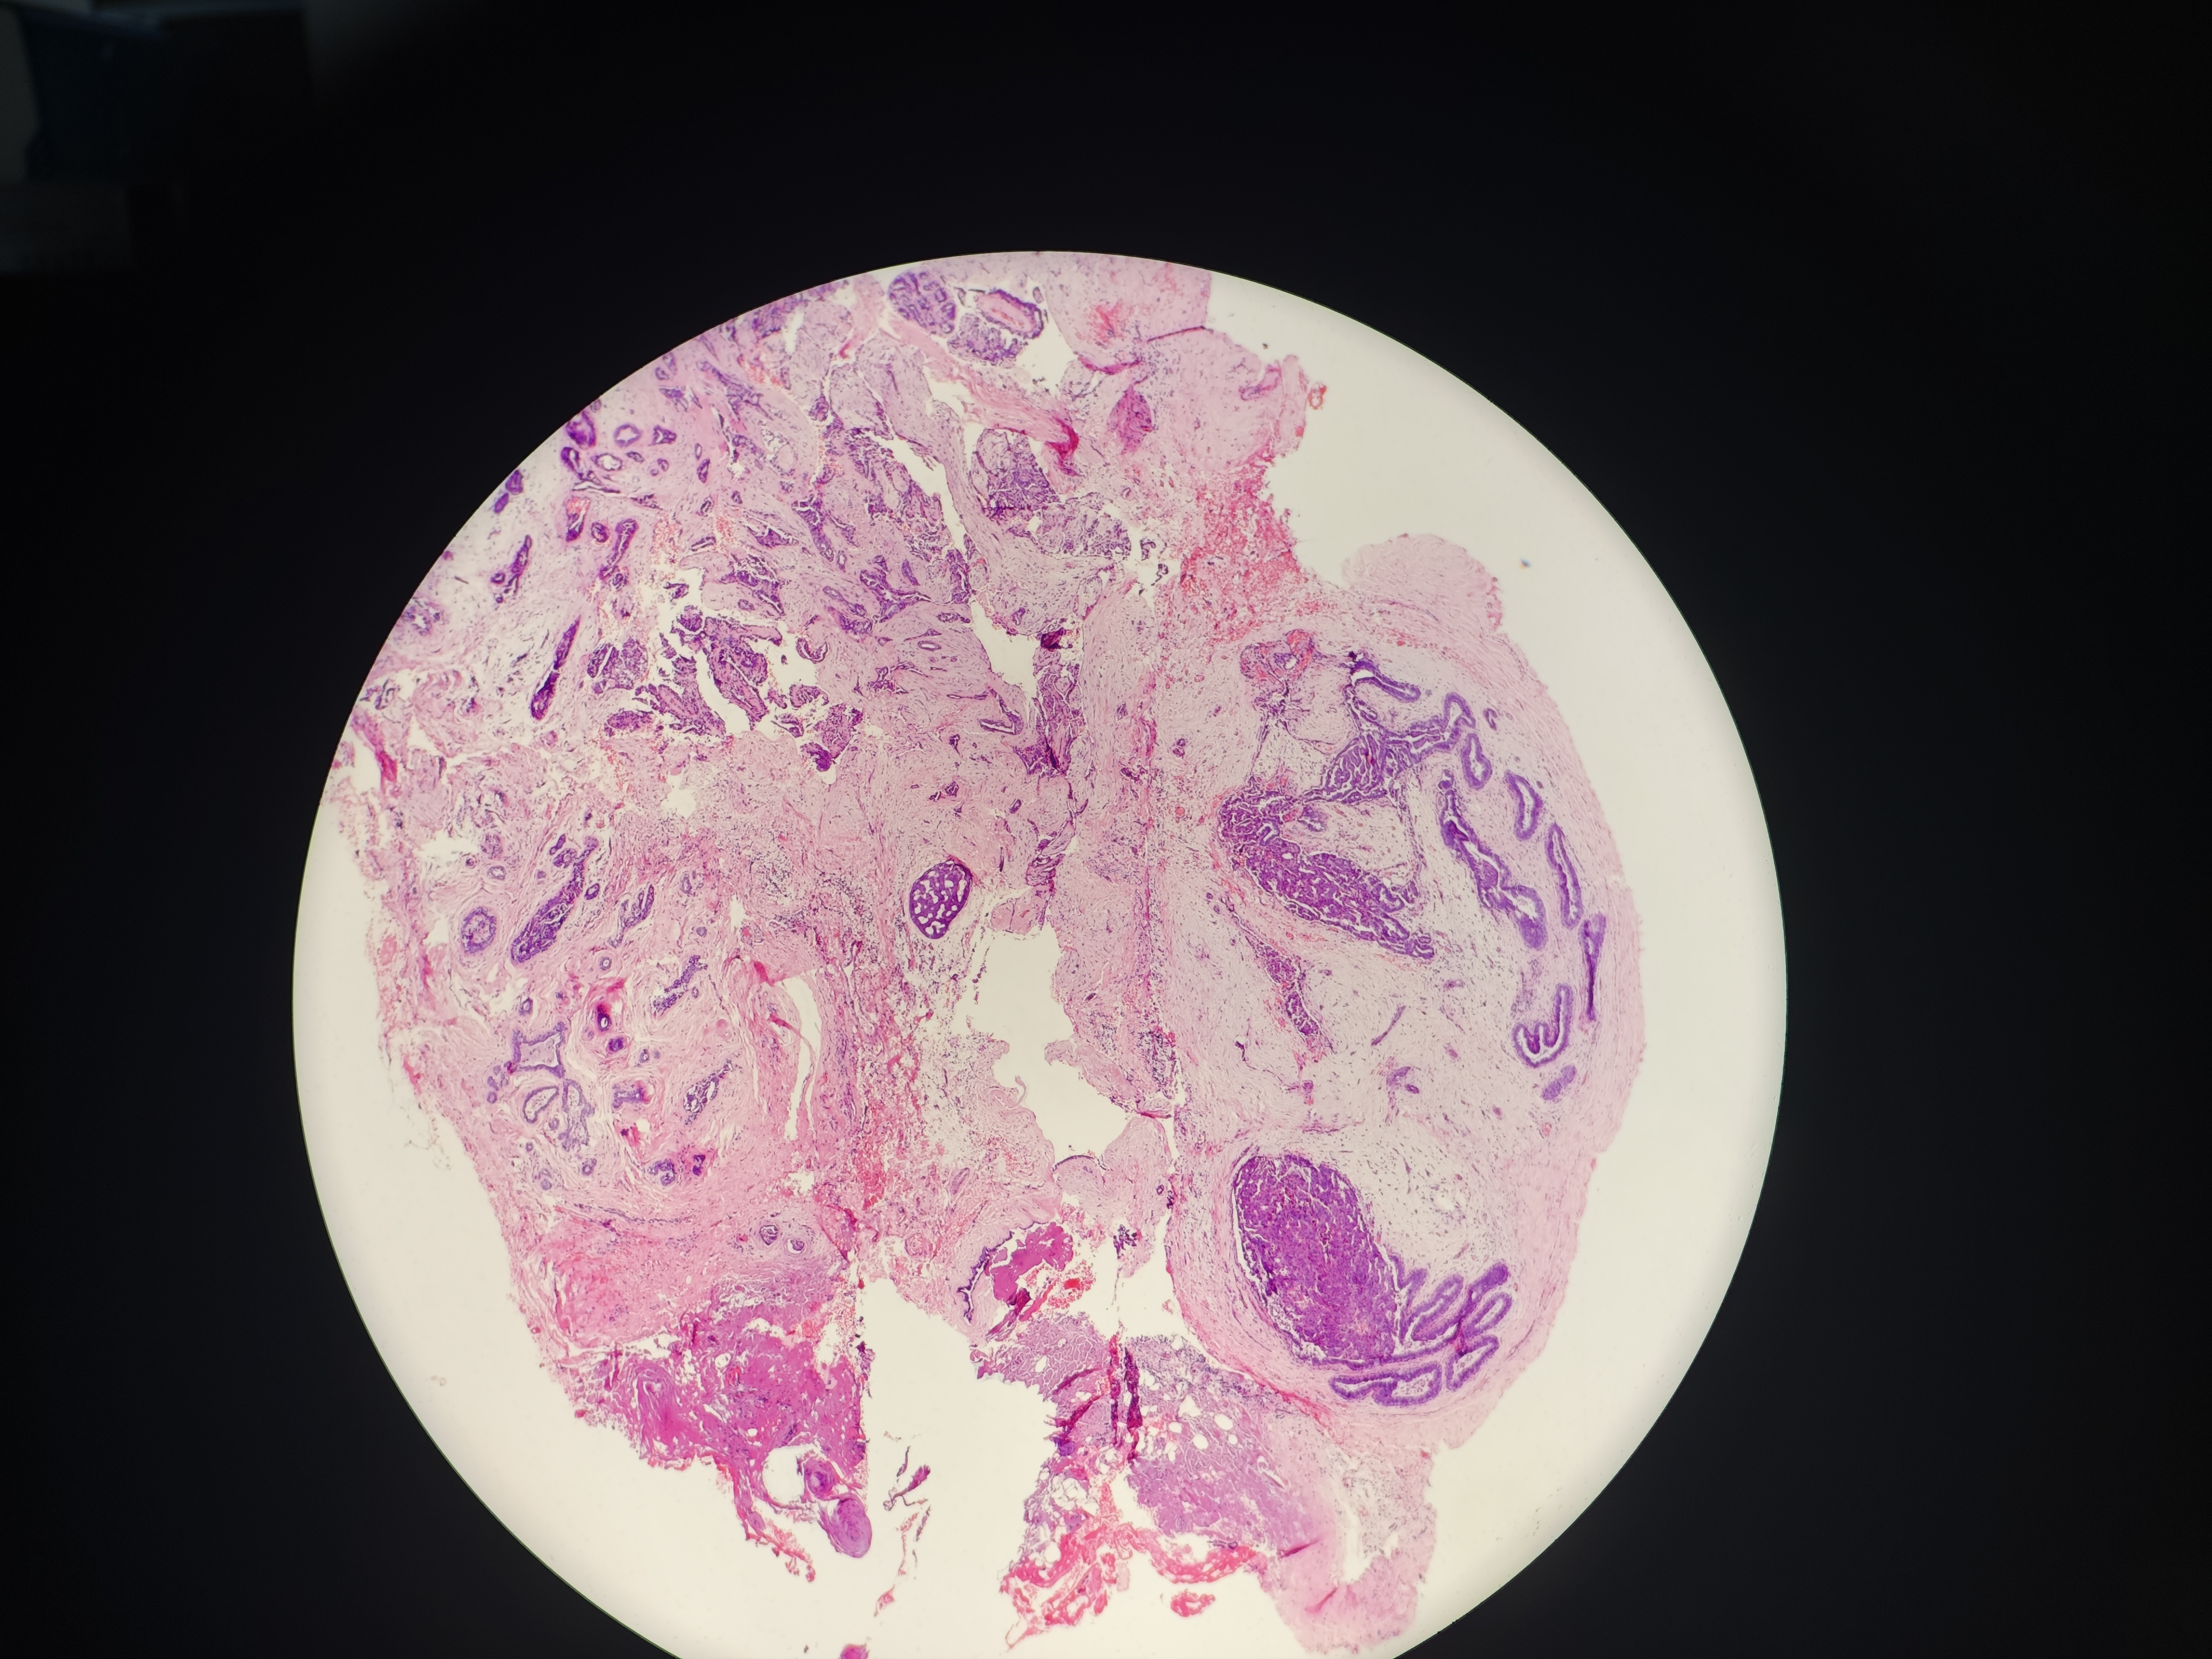

乳腺肿物

性别

女

年龄

38岁

乳腺彩超结果:右乳3点位实性结节BI-RADS 4a

右侧乳腺肿物

灰黄色软组织一块,1.3*1*0.6cm,切面见0.8×0.5×0.5cm的灰白灰红色肿物

各位老师,这个怎么报?报癌?

考虑:UDH